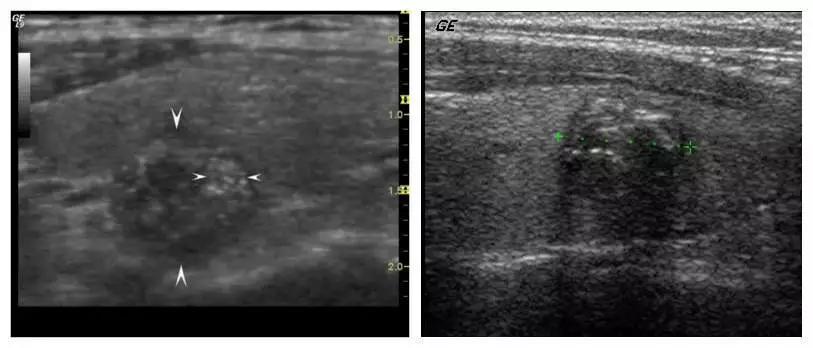

钙化结节的直径≤2 mm,超声表现多呈针尖样、颗粒样、点状、砂粒样。病理组织切片中观察圆形或砂粒体样直径60~100um。超声检查中≤2mm的钙化点反映的就是病理组织切片中观察到的微钙化,但超声检查的微小钙化发现率相对较低。

1、砂粒样钙化几乎为甲状腺恶性肿瘤所共有,常是乳头状癌的特征性表现。

目前普遍认为,微钙化是超声诊断甲状腺癌特异性最高的指标,文献报道为83%~90.3% ,对乳头状癌则可达93%~95%。